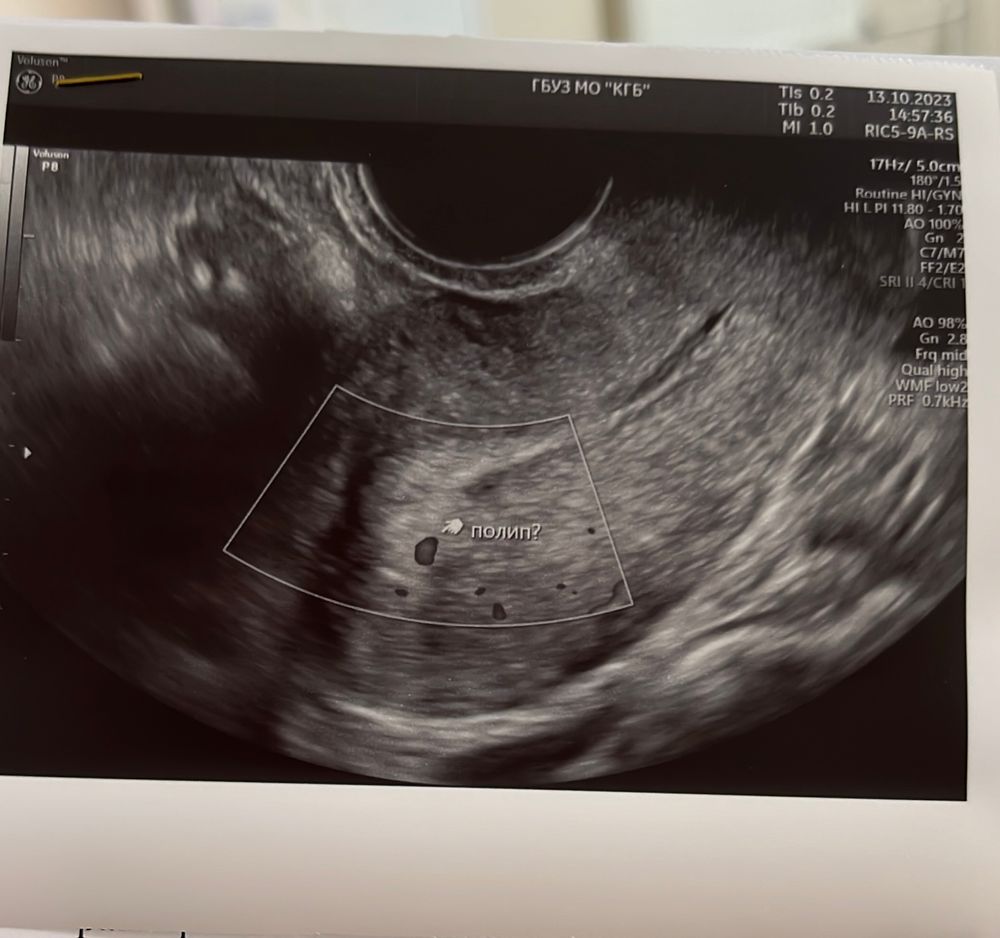

Провела сегодня повторное узи. Матка увеличилась, была 47*36*45, спустя 10 дней стала 52*40*54. Также анэхогенное включение. Врач даже размеры не измерила, спросила про тесты. Сказала отрицательные. Поставила под вопросом полип? Даже диагноз не прокомментировала, говорит все у врача спрашивайте. Диагноз : секретная фаза мц, признаки начальной формы аденомиоза и перенесенного эндометрита. Нельзя исключить полип. Назначила переделать узи после месячных и сдать хгч. Как то так… тесты так же отрицательные, только после высыхания что то просвечивается, наверное реагент. Врач моя ушла в отпуск, наверное жду месячных. Изображение Изображение Изображение

Anchi ,сходила на узи еще через 10 дней, опять было образование. В итоге пришли месячные с задержкой , после них сходила на узи. На узи вообще уже ничего не было. Врач сказала, что она уверена, что была замершая беременность, которая в эти месячные вышла.